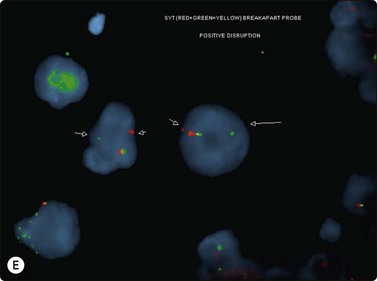

The most common sarcomas of this site include malignant fibrous histiocytoma and liposarcoma.131,132 Synovial sarcoma is well described.133 We have seen a single case of monophasic synovial sarcoma of mediastinum diagnosed on transoesophageal EUS FNB by the demonstration of SYT-SSX fusion transcripts by FISH on cell blocks, indicating X:18 translocation (all material shown here is courtesy of Dr. Anita Soma, PathWest QE II AP). (Fig. 9.10) The patient was a 45-year-old male with an 11-cm mass adjacent to the lower oesophagus, displacing the heart. Smears showed a rather bland spindle cell population but with mitotic activity. The cell block immunohistochemistry was negative for cytokeratins, CD117 and smooth muscle markers, making leiomyosarcoma and GIST unlikely. The tumor did show positive staining for CD99, BCL2 and CD34, raising the possibility of solitary fibrous tumor or synovial sarcoma. An SYT-SSX1 fusion transcript was detected by reverse transcriptase PCR, reinforcing the FISH cytogenetics. No other diagnostic procedures were undertaken (Fig 9.10).

Fig. 9.10 Synovial sarcoma

(A) Large infiltrative mass posterior to heart (Thoracic CT); (B) Loose fascicle of spindle cells including small blood vessels. Background of bare tumor nuclei (H&E, LP); (C) Loose cluster of bland spindle cells but with mitotic activity (H&E, HP); (D) Cell block, small spindle tumor cells with non-specific features (H&E, HP);(E) FISH on cell block, breakapart probe for SYT showing positive disruption of red-green-yellow components (FISH, HP); (F) FISH on cell block, fusion probe for SSX2 (green) and SYT (red) probes showing positive fusion of green and red components. (FISH, HP); (G) FISH on cell block, fusion probe for SSX2 (green) and SYT (red) probes showing positive fusion of green and red components (FISH, HP).